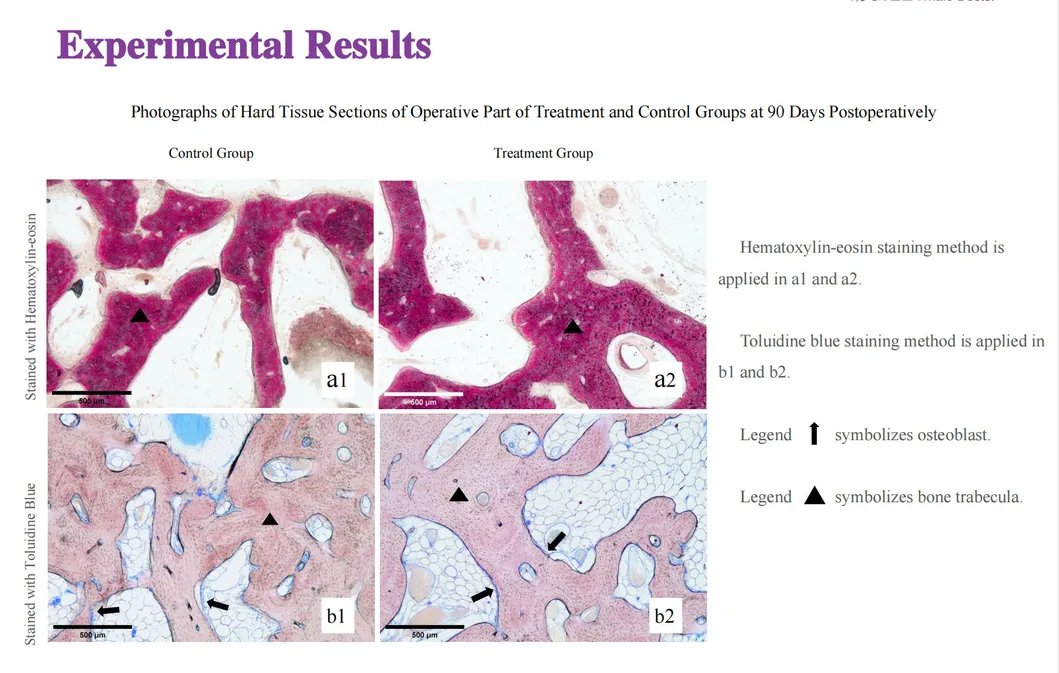

This study evaluated the effectiveness of state-of-the-art dental tools for veterinary use. The treatment group utilized the revolutionary Pneumatic Dental Elevator Kit. Critical factors observed included physiological parameters, intraoperative complications, extraction duration, and socket damage. Rigorous statistical analysis highlights the superior performance of these advanced tools.